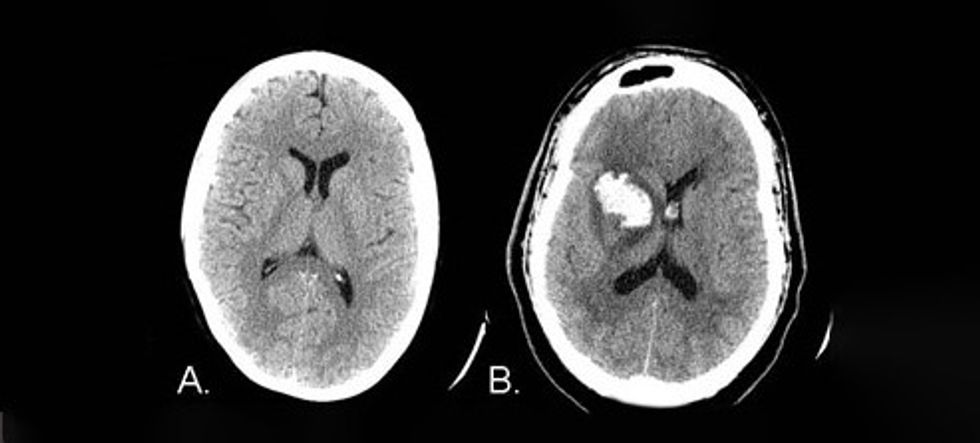

Sindromat e zhvilluar nga infarkti trunor bazohen në pasqyrën klinike dhe mundë të redefinohen përmes tomografisë së kompjuterizuar të trurit. Ato japin informacion për lokalizimin anatomik dhe vaskular, etiologjinë dhe prognozën.